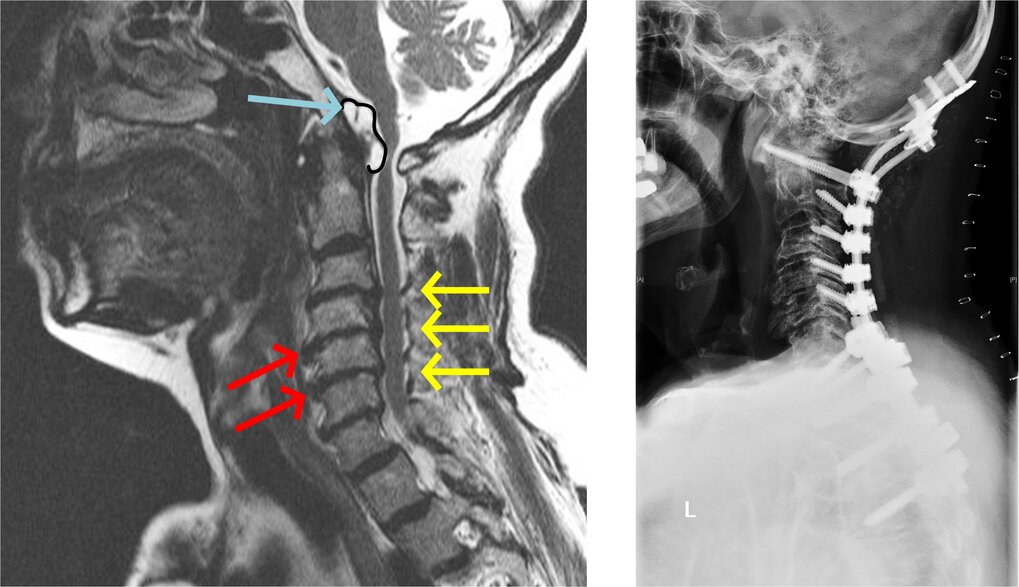

Abb. links: MRT einer Halswirbelsäule. Die blauen Pfeile zeigen eine rheumatisch bedingte Weichteilwucherung am Übergang zwischen der Halswirbelsäule und dem Schädel. Zusätzlich fallen Verschleißerscheinungen der mittleren Halswirbelsäule auf, in Form von knöchernen Ausziehungen (Osteophyten - rote Pfeile) und Bandscheibenvorwölbungen die den Spinalkanal und damit das Rückenmark einengen (gelbe Pfeile).

Abb. rechts: Kontrollröntgen nach der Stabilisierung und Beseitigung der Engstellen. Trotz der langstreckigen Versteifung hatte der Patient deutlich weniger Nacken- und Nervenschmerzen.